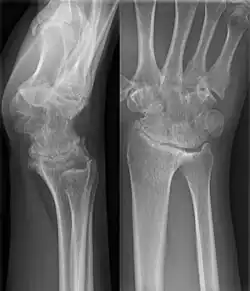

Eine karpale Koalition ist eine feste Verbindung zwischen Handwurzelknochen, die normalerweise über ein Gelenk in Kontakt stehen. Dabei kann diese Verbindung knöchern (Synostose), knorpelig (Synchondrose) oder bindegewebig (Syndesmose) ausgebildet sein. Als Ursache wird von einer mangelhaften Differenzierung der Handwurzelknochen zwischen der 4. und 8. Embryonalwoche ausgegangen[1].

Wenn eine karpale Koalition isoliert auftritt, was der häufigere Fall ist, sind in der Regel zwei Knochen der gleichen Handwurzelreihe betroffen, beim Auftreten im Rahmen von Syndromen oder anderen globaleren Störungen treten auch Verbindungen von mehreren Knochen beider Reihen auf[1][5]. Die bei Weitem am häufigsten verschmolzenen Knochen der Handwurzel sind Os lunatum und Os triquetrum gefolgt vom Os hamatum mit dem Os capitatum[1].

Eine Verschmelzung der Handwurzelknochen kann auch sekundär bei entzündlichen Erkrankungen wie z. B. der juvenilen idiopathischen Arthritis auftreten.